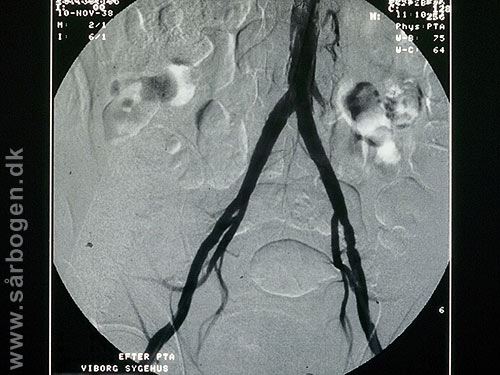

Zoom

Efter PTA af iliacak...

Før PTA af iliacakar...